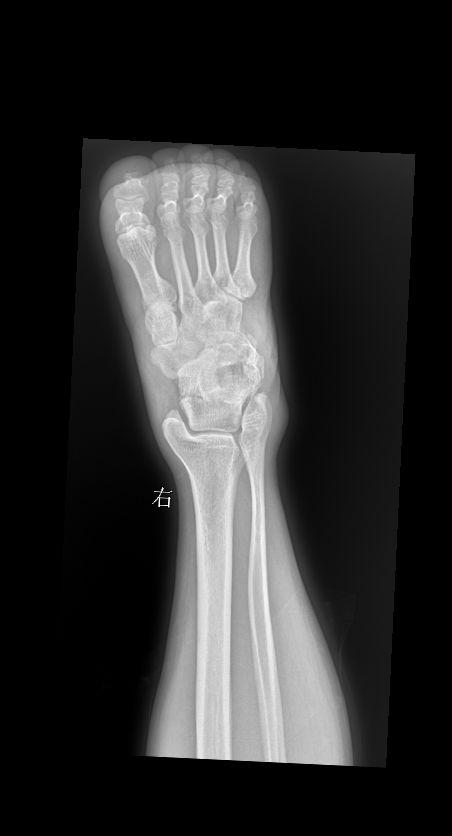

腕关节扭伤三天就诊 男 73y